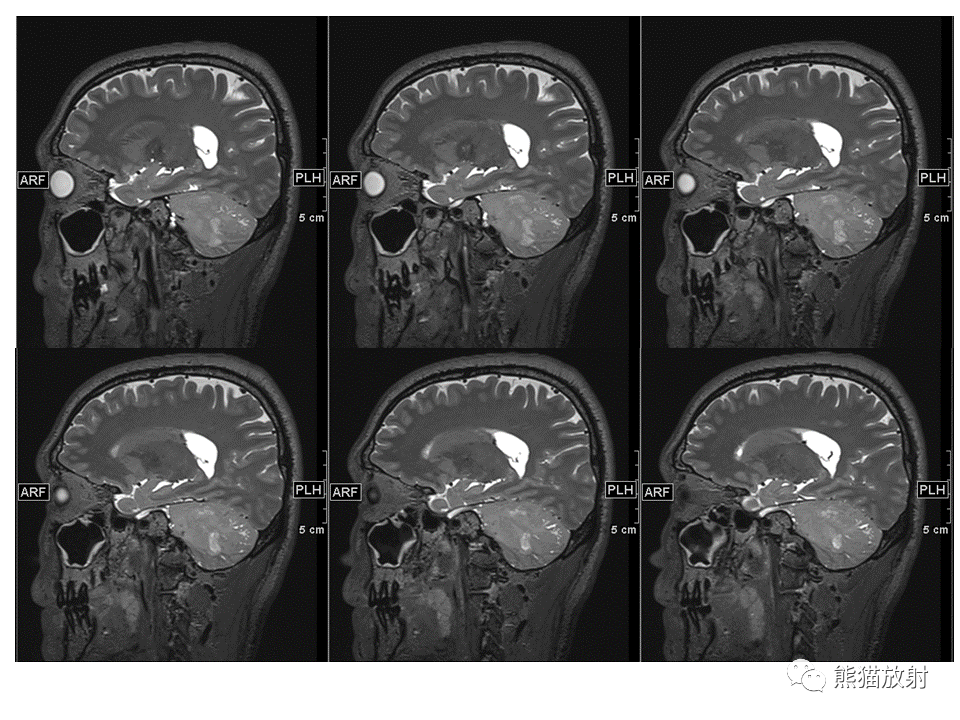

【PPT】小脑发育不良性神经节细胞瘤 VS 成人型髓母细胞瘤-2